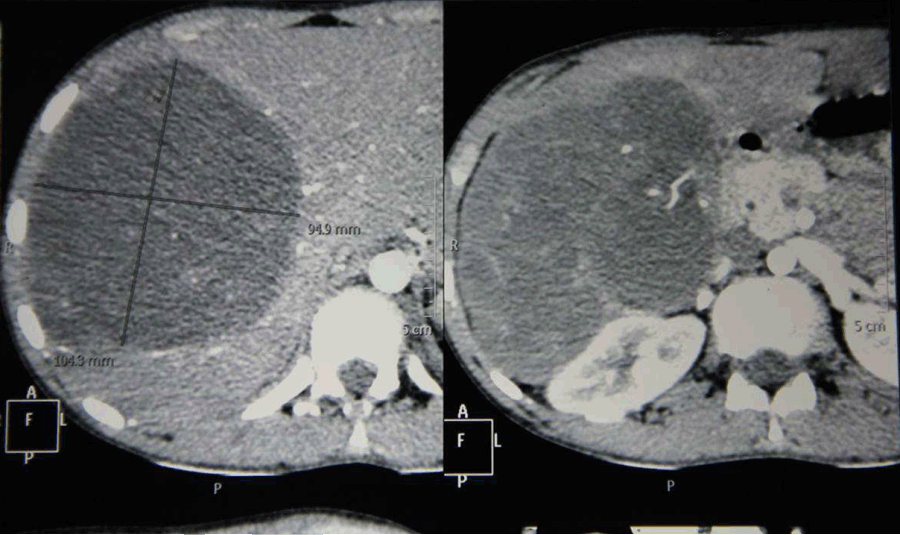

A 16-year-old boy with body weight of 26 kg was presented to us with a mass in the right hypochondrium since one month with history of abdominal pain, fever with chills and rigors. He had no history of jaundice, weight loss or loss of appetite. On elaborating the history, the mass was present for the last one month and rapidly increased for the last one week with severe intolerable pain last four days. On clinical examination, abdomen was soft and minimal guarding was present. A firm tender hepatomegaly was present 6 cm below right costal margin. Surface found to be smooth and edges were rounded. Contrast-enhanced computed tomography scan of abdomen revealed 15x11x9 cm heterogeneous multi-septated lobulated mass lesion involving right lobe of liver involving the segments 5, 6, 7, 8 (Figure 1) and (Figure 2). Portal venous Doppler study showed displaced and stretched right portal vein with normal flow. Laboratory investigations at the time of admission showed hemoglobin 8 g/dL, platelets 4 lakhs/mm3, blood sugar 80 mg/dL, blood urea 22 mg/dL and serum creatinine 0.8 mg/dL. Two units of packed cells were transfused and the preoperative hemoglobin was 10 mg/dl. Tumor markers AFP and CA 19-9 were done. Alpha fetoprotein value was 4 ng/mL and CA 19–9 was found to 20 U/mL. Liver biopsy was not taken to avoid the risk of seedling of an operable tumor.

Figure 1: Contrast-enhanced computed tomography scan of abdomen showing heterogenous mass lesion in right lobe of liver.